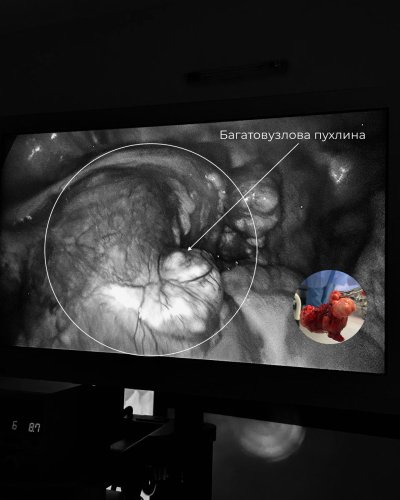

За результатами обстежень було вирішено провести операцію. Під час діагностичної лапароскопії лікарі виявили, що з рудименту матки утворилася пухлина, що нагадувала вузлову міому. Найбільший вузол досягав розміру 7-8 см, а поруч були й менші утворення. Оскільки пухлина могла спричинити больовий синдром, перекручування вузлів або навіть бути злоякісною, було ухвалене рішення про проведення операції.

«Такий випадок вкрай рідкісний. Подібний описувався в американській літературі лише один раз. Операція була надзвичайно складною. На неї зійшлося все відділення, адже подібного в нашій практиці ще не траплялося. Цей випадок унікальний не лише для нашої лікарні, а й для української хірургічної гінекології загалом», — каже Юлія Овечко, завідувачка гінекологічного відділення Лікарні Святого Пантелеймона.